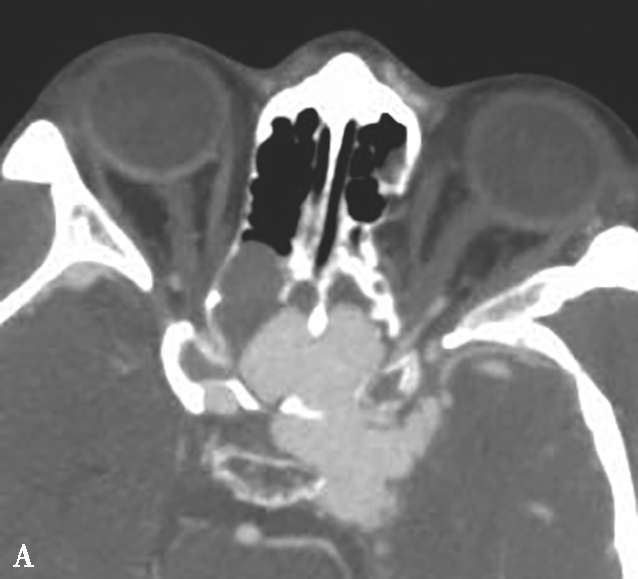

图1-2-5 青少年非角化型鼻咽癌

患者男,14岁,反复间断鼻出血、头晕头痛20余天。A.鼻窦CT横断面骨窗,示鼻咽顶后壁左侧软组织肿块,累及后鼻孔区,邻近左侧岩尖、蝶骨翼突骨质破坏、不完整,边缘毛糙;B.鼻窦CT冠状面重组骨窗,示左侧鼻咽顶后壁软组织肿块,邻近蝶骨翼突溶骨性骨质破坏,累及蝶骨体,边缘毛糙不整;C.鼻咽部MR T 2 WI横断面,示鼻咽左侧壁软组织肿块呈不均匀稍高信号,其间可见条状高信号,未见血管流空影;病变累及左侧翼内肌、窦后脂肪间隙;左侧上颌窦内可见积液呈明显高信号;D.鼻咽部MR T 1 WI横断面,示鼻咽部软组织肿块呈等信号,左侧上颌窦内积液呈低信号;E.鼻咽部MR T 1 WI横断面增强脂肪抑制序列,示鼻咽部病变呈明显强化,累及鼻咽左侧壁、顶后壁并跨越中线累及右侧咽隐窝,右侧咽后间隙淋巴结可见,与软组织肿块同步强化;F.鼻咽部MR T 1 WI冠状面增强脂肪抑制序列,示病变累及左侧咽旁间隙,左侧上颌神经明显增粗强化,并经上颌神经累及左侧海绵窦致其增厚、强化。活检病理符合鼻咽癌(非角化型)